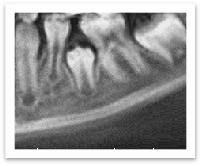

另外,在正常的牙和牙中间有时候会有多生的额外牙或牙瘤,它们会成为恒牙正常萌出的拦路虎。所以,需要借助外科手段把它们去除掉。

图中箭头所示多生牙,影响恒牙萌出